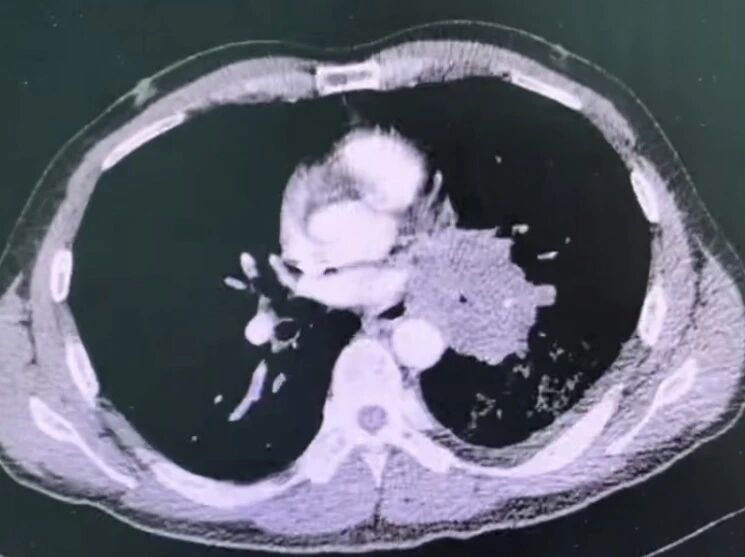

胸部ct提示左肺门巨大占位,包绕肺门主要结构

肿瘤靠近心脏大血管,依然有机会切干净。患者肿瘤位于肺门,紧邻心脏与大血管,常规手术风险极高。胡学飞主任最终实施了心包内左全肺切除+纵隔淋巴结清扫,在扩大切除范围的同时保证安全,实现完整根治。